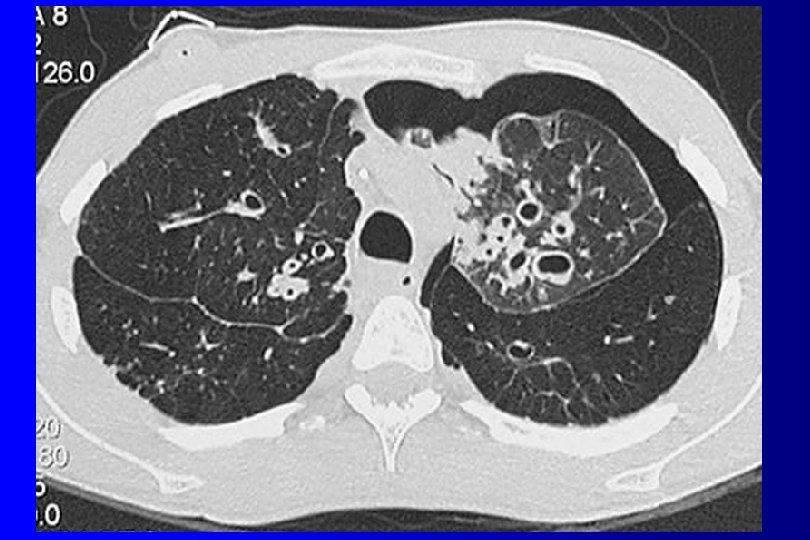

PLEUMOTHORAX imagerie üRadios standard (inspiration et en expiration forcée en cas de doute): hyperclarté entre la paroi et le parenchyme üTomodensitométrie (scanner recherche de bulles)